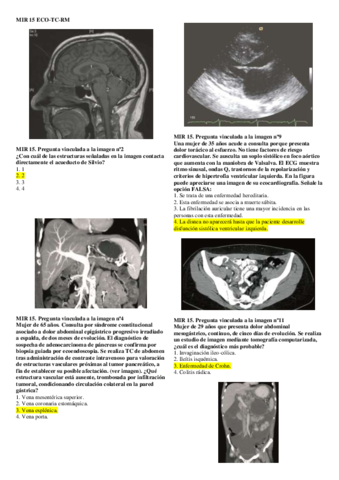

S02-MIR-2015-Gine-Eco-TC-RM-Alumnos.pdf